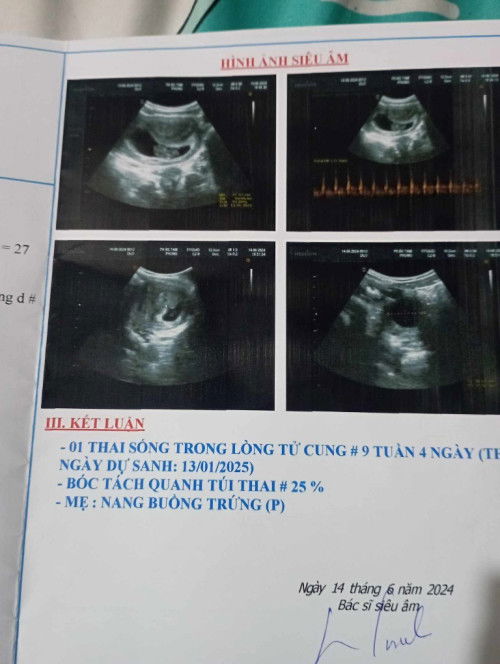

E thai 10 tuần bị bóc tách 25%

Thai 10 tuần bị bóc tách 25% đã hết ra huyết 2 ngày rồi , e đi siêu âm lại thì bé bình thường nhưng khi ăn vào là bụng lại đau lăm răm thì có sao k các mom

Vợ em mang thai 10 tuần bị bóc tách 25% , nhưng bé vẫn khoẻ bình thường , thì có nguy hiểm k ạ

Thai 10 tuần bóc tách 25% , nhưng tim thai và bé vẫn bình thường